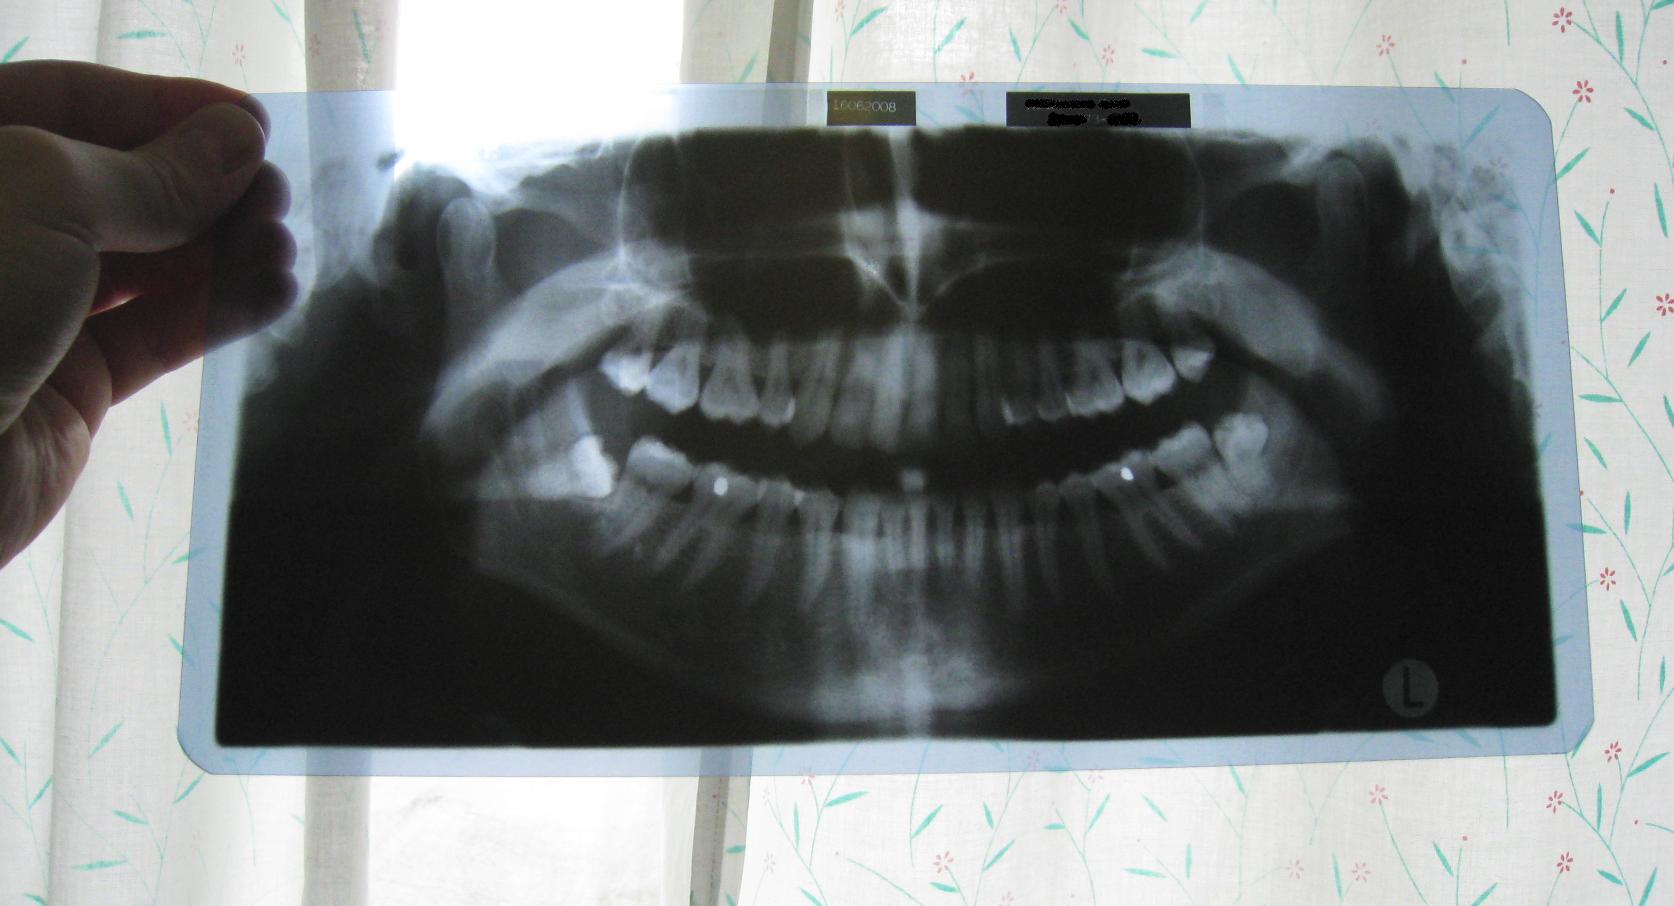

Tässä mun leegot. Kipeä hammas on siis toi kuvan oikea puoli eikä vasen puoli niinkuin luulin aluksi.